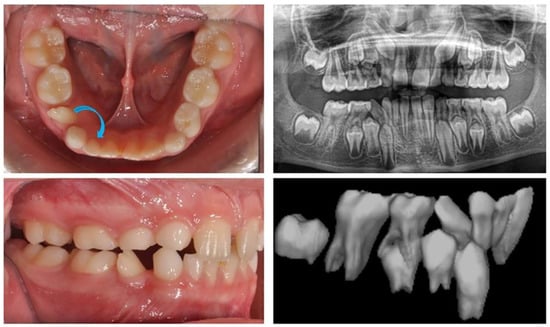

The first clinical case is that of an 8-year-old girl with an ectopic eruption of the lower-right lateral (42) in the area of the first temporary molar. In the lower dental arch, the temporary right lateral incisor and canine are in preserved positions. After an X-ray examination, hypodontia of the upper laterals was established in the upper dental arch. A well-developed and normally positioned germ of right canines and premolars in the lower was found (Figure 1). In this early phase of mixed dentition, the ectopically erupted lower-right lateral incisor should be positioned in its normal location. This will prevent future canine transposition or canine retention due to the mechanical barrier that the lateral presents. At the same time, it is important to preserve the perimeter of the dental arch in the case of the premature exfoliation of the temporary canine.

Figure 1. Oral clinical status and X-ray examinations of a patient with an ectopic eruption of the lower-right lateral (42) in the area of the first temporary molar. The blue arrow show the natural position of lower right lateral incisor.